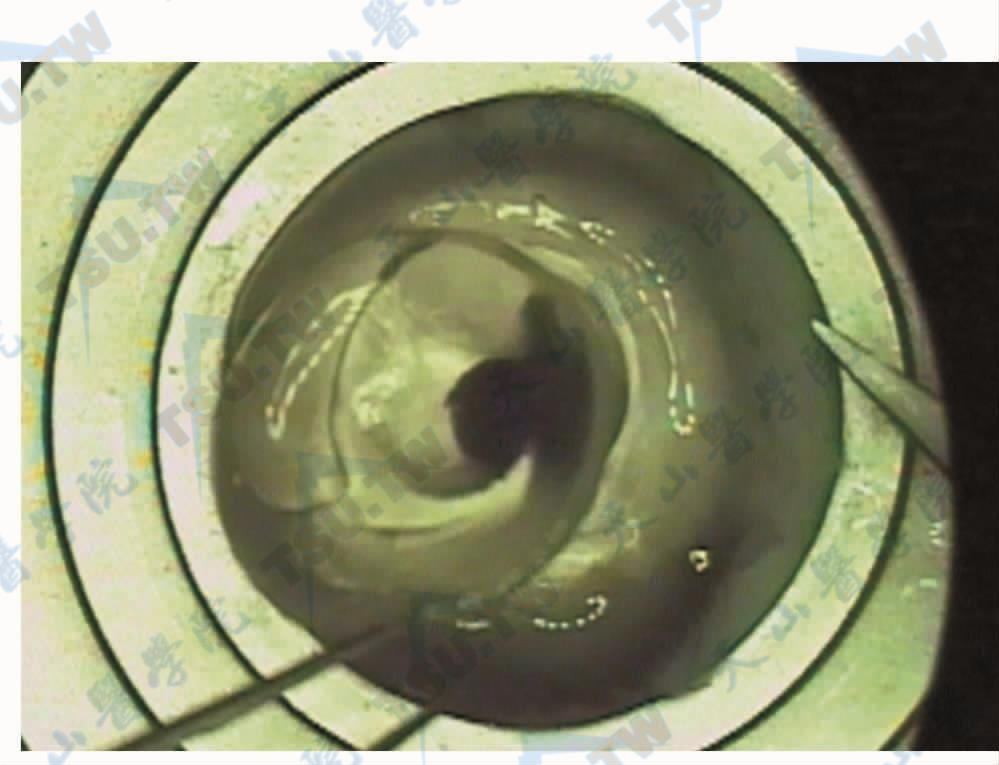

穿透性角膜移植术是一种通过替换受损或不透明的角膜组织来恢复视力的手术。它被广泛应用于治疗各种角膜疾病,如先天性角膜混浊、角膜溃疡和角膜营养不良等。手术过程中,医生会将捐赠者的健康角膜组织移植到患者眼部,以恢复其正常视力。

近期的研究表明,部分接受穿透性角膜移植术的患者在手术后出现了青光眼。青光眼是一种眼部疾病,会导致眼内压力升高,损害视神经,最终可能导致失明。